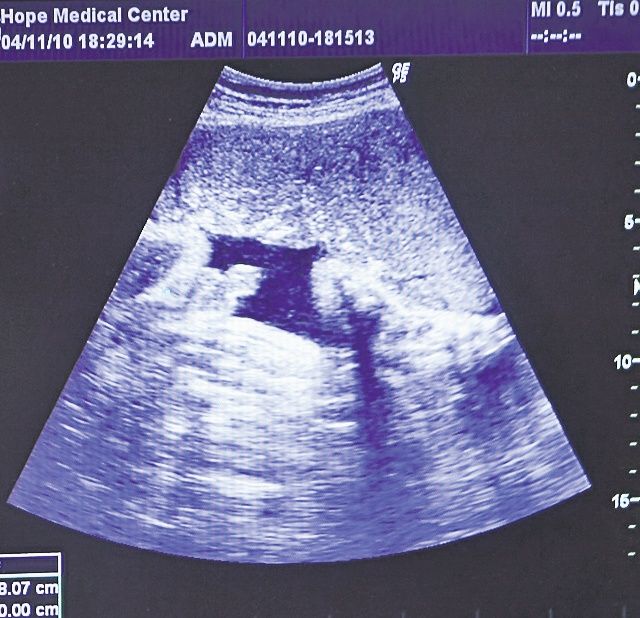

Adriana Bahmuţeanu a fost joi seara la un control de rutină, înainte de a naşte. Soţia lui Prigoană, însărcinată în luna a opta, şi-a făcut o ecografie pentru a afla dacă băieţelul pe care îl va aduce pe lume la începutul lunii viitoare, la Spitalul Polizu, se dezvoltă normal. Bahmu a mers la centrul medical Hope Medical Clinic, din Bucureşti, unde medicul Horia Cioflan i-a făcut o ecografie şi alte analize.

“Sunt bucuroasă că sarcina decurge bine, copilul are acum 1.800 de grame şi am scăpat de perioada critică. Mai am cam o lună până nasc şi trebuie să stau liniştită în pat, pentru a duce sarcina la capăt cu bine. Din ce am văzut eu la ecograf, copilul seamănă cu mine de această dată, are nasul meu şi trăsăturile mele la faţă”, ne-a spus Bahmu.